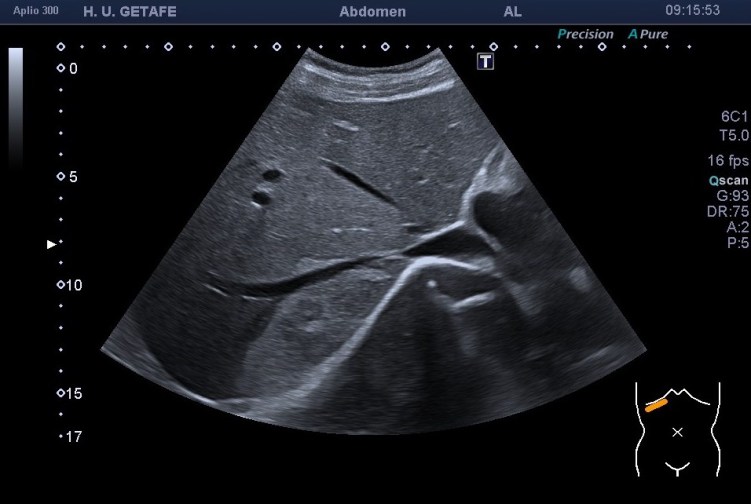

Te dejo las imágenes, estúdialas, luego las comento:

Bien, en el caso de hoy te presento un hemangioma atípico. Es hiperecogénico, pero su tamaño excede por tres el tamaño máximo de estas piezas patológicas ocupantes de espacio en el hígado. Está en torno a los 9 centímetros. Ligeramente heterogéneo este hemangioma es muy bonito porque rodea a una de las ramas de las suprahepáticas, como puedes ver en la imagen 1 y 2, en el corte axial se observa perfectamente.